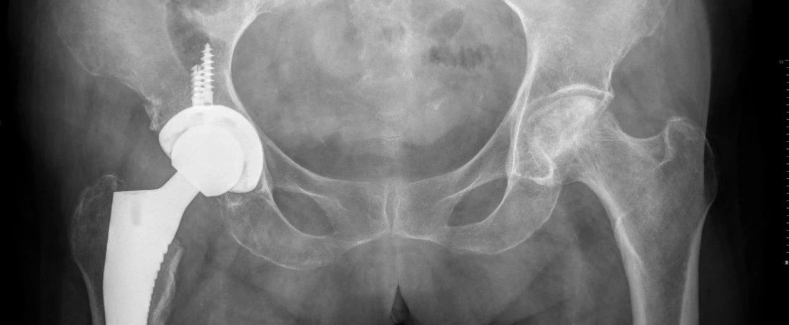

人工髋膝关节置换术流程化管理

2020中国嵩山人工髋关节翻修高峰论坛会议